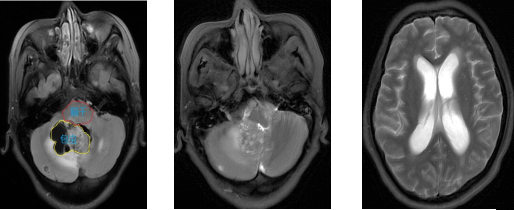

色**是一名48岁的中年女性。因“头痛,呕吐,阵发性意识丧失1月”就诊于我院神经外科。头颅MRI提示:颅内多发占位,其中位于右侧小脑及第四脑室内,脑干旁的病变体积最大,直径达3.8cm, 病变阻塞脑脊液循环通路,导致梗阻性脑积水。

术前MRI影像提示脑深部包虫病变伴梗阻性脑积水

术后复查MRI 提示病变切除满意,脑积水缓解。

术后MRI影像